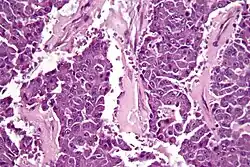

| Micrograph of an acinar cell carcinoma of the pancreas. H&E stain. | |

Histomorphologically, the tumour resembles the cells of the pancreatic acini and, typically, have moderate granular cytoplasm that stain with both PAS and PASD.[4]

Light microscopy of an acinar cell carcinoma biopsy typically shows granular appearance.[6] Immunohistochemistry is usually positive for trypsin, chymotrypsin and lipase.[6] On genetic testing, altered genes/proteins are typically found for p53, SMAD4, APC, ARID1A and GNAS.[6]